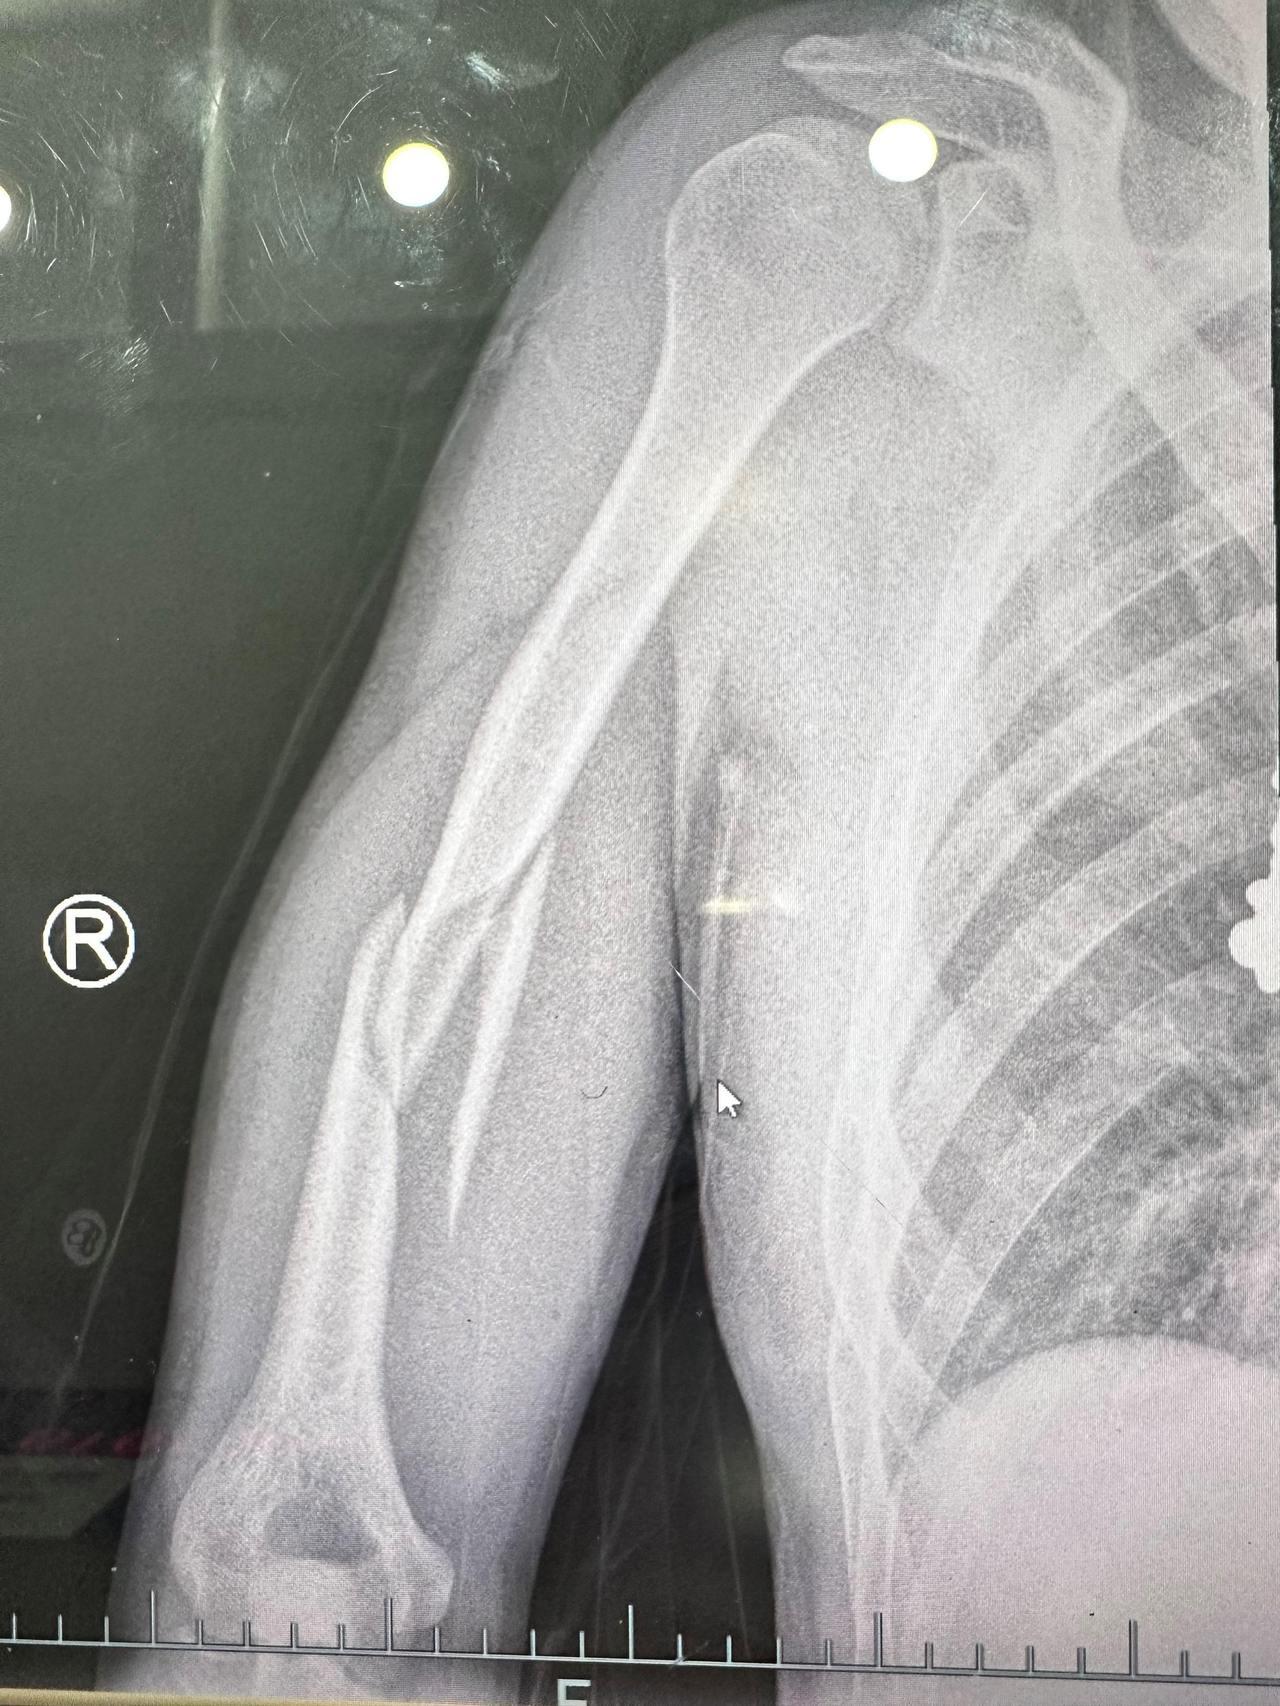

接诊的急诊科医生邵尉在详细询问病情后,迅速为小胡安排了X光射线检查。

影像显示,小胡发生了“肱骨干断裂”而且周围软组织明显肿胀,情况十分严重。

由于小胡螺旋形骨折移位太严重,没办法保守治疗,最后不得不采用了手术用钢板内固定,在右臂上留下了一道20多公分的伤疤,需要很长时间康复。原本欢乐的宵夜时光,却以骨折住院收场,实在令人始料未及。